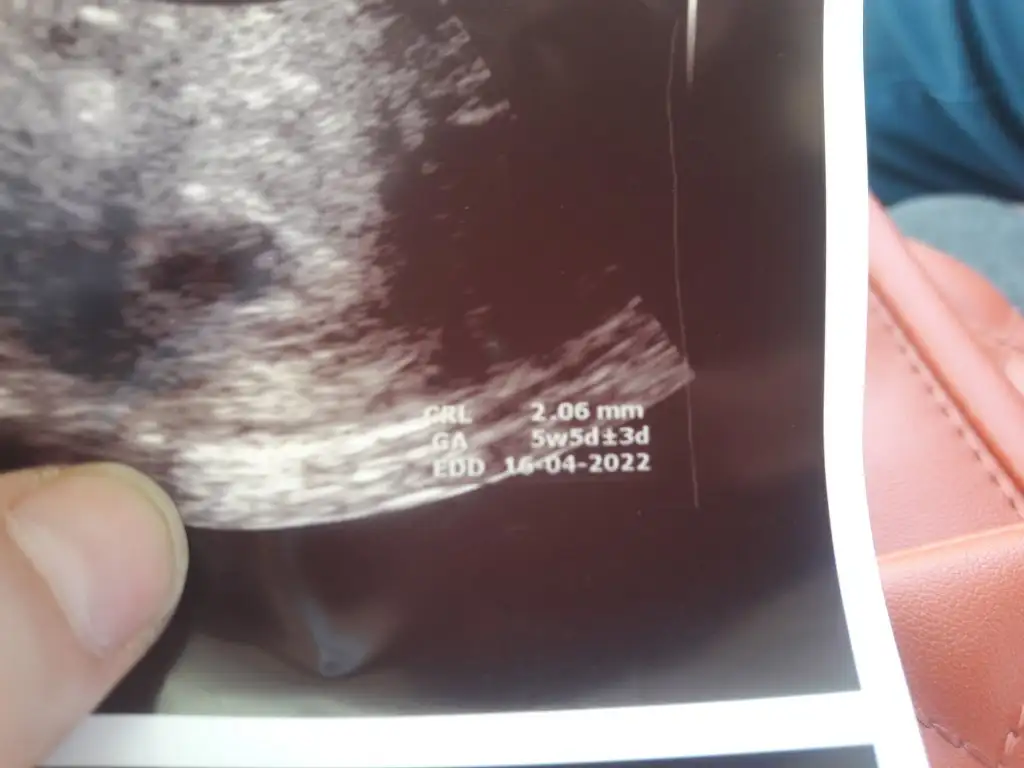

Bende de kese var yolk var fetusta 2.06 diye işaretledi.benimde bende geçici menepoza soktogunda bir kez adet getirici ilaç verdi adetliyken göreyim dedi yani 22haziran benimde son adet tarihim seninle aynı sayılırız bak sana iki tane ultrason kağıdımı aticam 10gun arayla olan